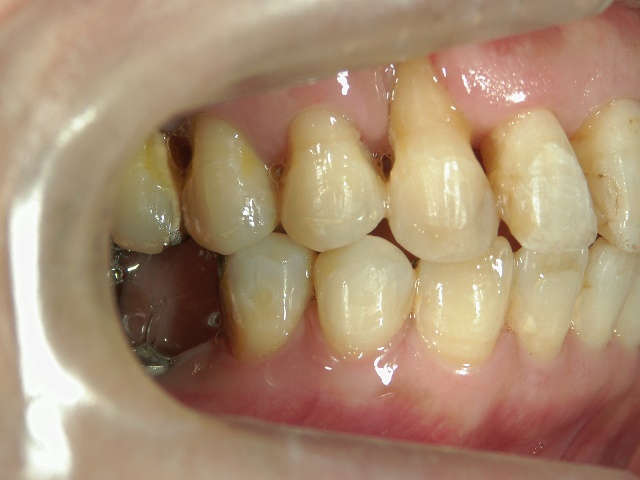

矯正歯科 治療前